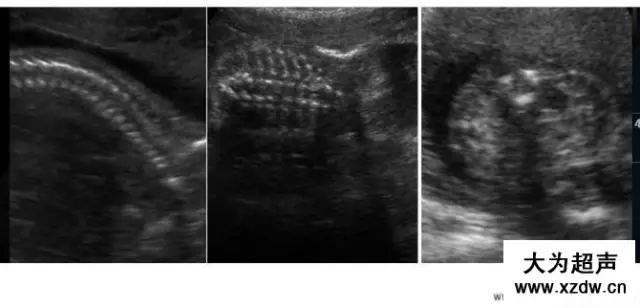

產科超聲正常圖片